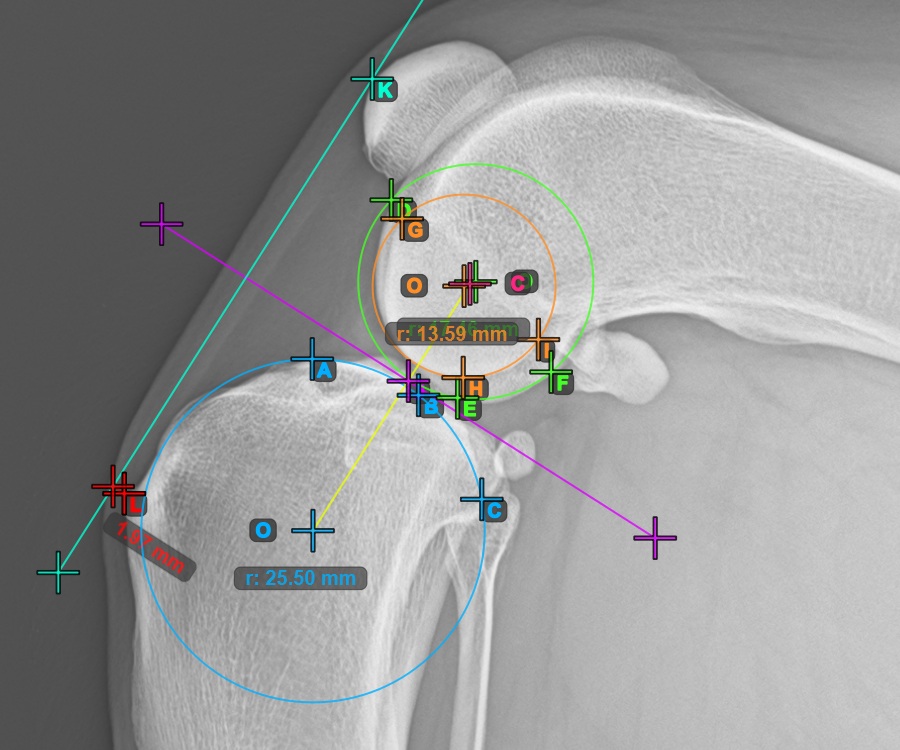

Markieren Sie zusätzlich die drei Punkte auf der Gelenkfläche des zweiten Condylus Femoris.

Markieren Sie die drei Punkte am inneren (sekundären) Kondylus des Oberschenkelknochens (Condylus Femoris). Unabhängig von der Reihenfolge stellen Sie sicher, dass Sie den vordersten Punkt, den hintersten Punkt und den Mittelpunkt des Condylus Femoris markieren. Basierend auf den drei gesetzten Punkten wird automatisch ein Kreis konstruiert.

Das Bild unten zeigt die typische Platzierung der drei Punkte am zweiten Condylus Femoris.